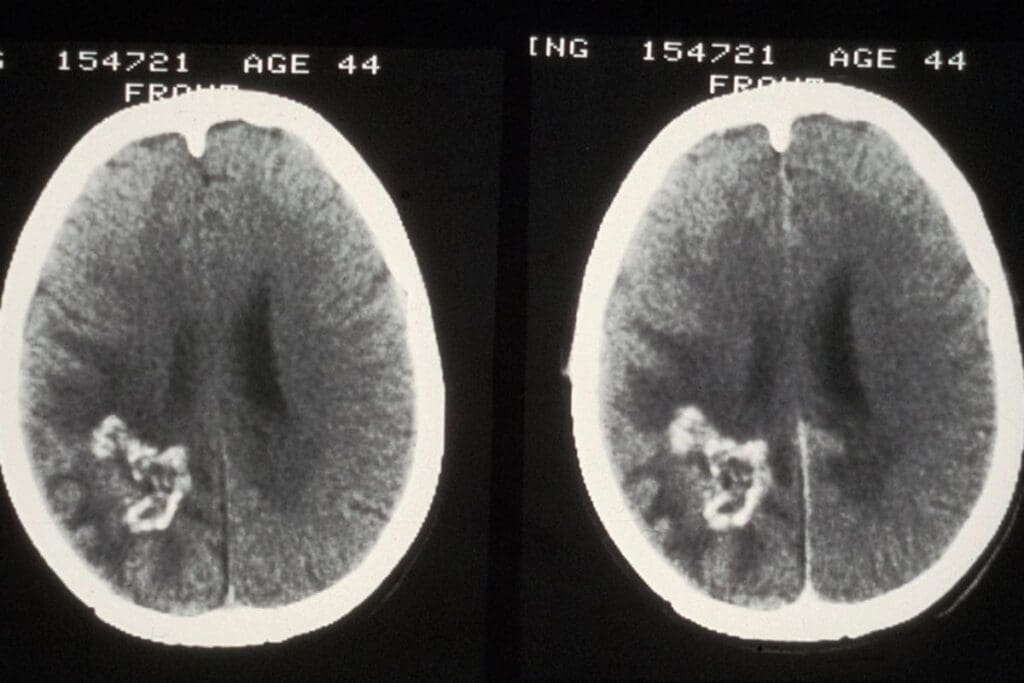

A CT urogram has several phases, each showing the urinary tract at different times. The non-contrast phase gives us a starting point. The nephrographic phase focuses on the kidney’s inner parts. The excretory phase shows how the contrast moves through the system, highlighting any blockages or issues.

CT urogram is designed to check the urinary tract. It has several phases, starting with a non-contrast phase and then contrast-enhanced phases. Standard CT scans, on the other hand, can be set up for many different needs. They might use non-contrast or contrast-enhanced protocols.

- CT urogram has multiple phases for detailed urinary tract images

- Standard CT scans might have just one phase, depending on the need

- CT urogram focuses on the urinary tract, while standard CT scans can look at different body parts